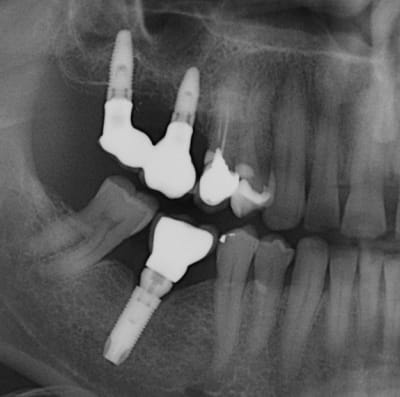

L'image de l'implant qui a cassé en apical, reprise quelques temps après avec une scie cloche, repose et radio à 5 ans.

Malgré une adaptation prothétique inadéquate, pas de gros problème.

Je précise qu'avant la "fracture" de l'implant, la résorption osseuse allait jusqu'à la partie cassée.

Ce qui est étonnant dans ce cas, c'est que le patient implanté dans les années 96, a perdu ses 3 ou 4 implants (je n'ai pas la fiche) pour cause de peri-implantite (ma première) et ce aussi bien sur du cylindrique que sur du Tatum D4 (20mmx 7 x 4.5)donc avec très gros dégâts à la dépose, et malgré ça le patient voulait du fixe, j'ai ré-implanté ( 6 implants) et plus aucun problème depuis ...